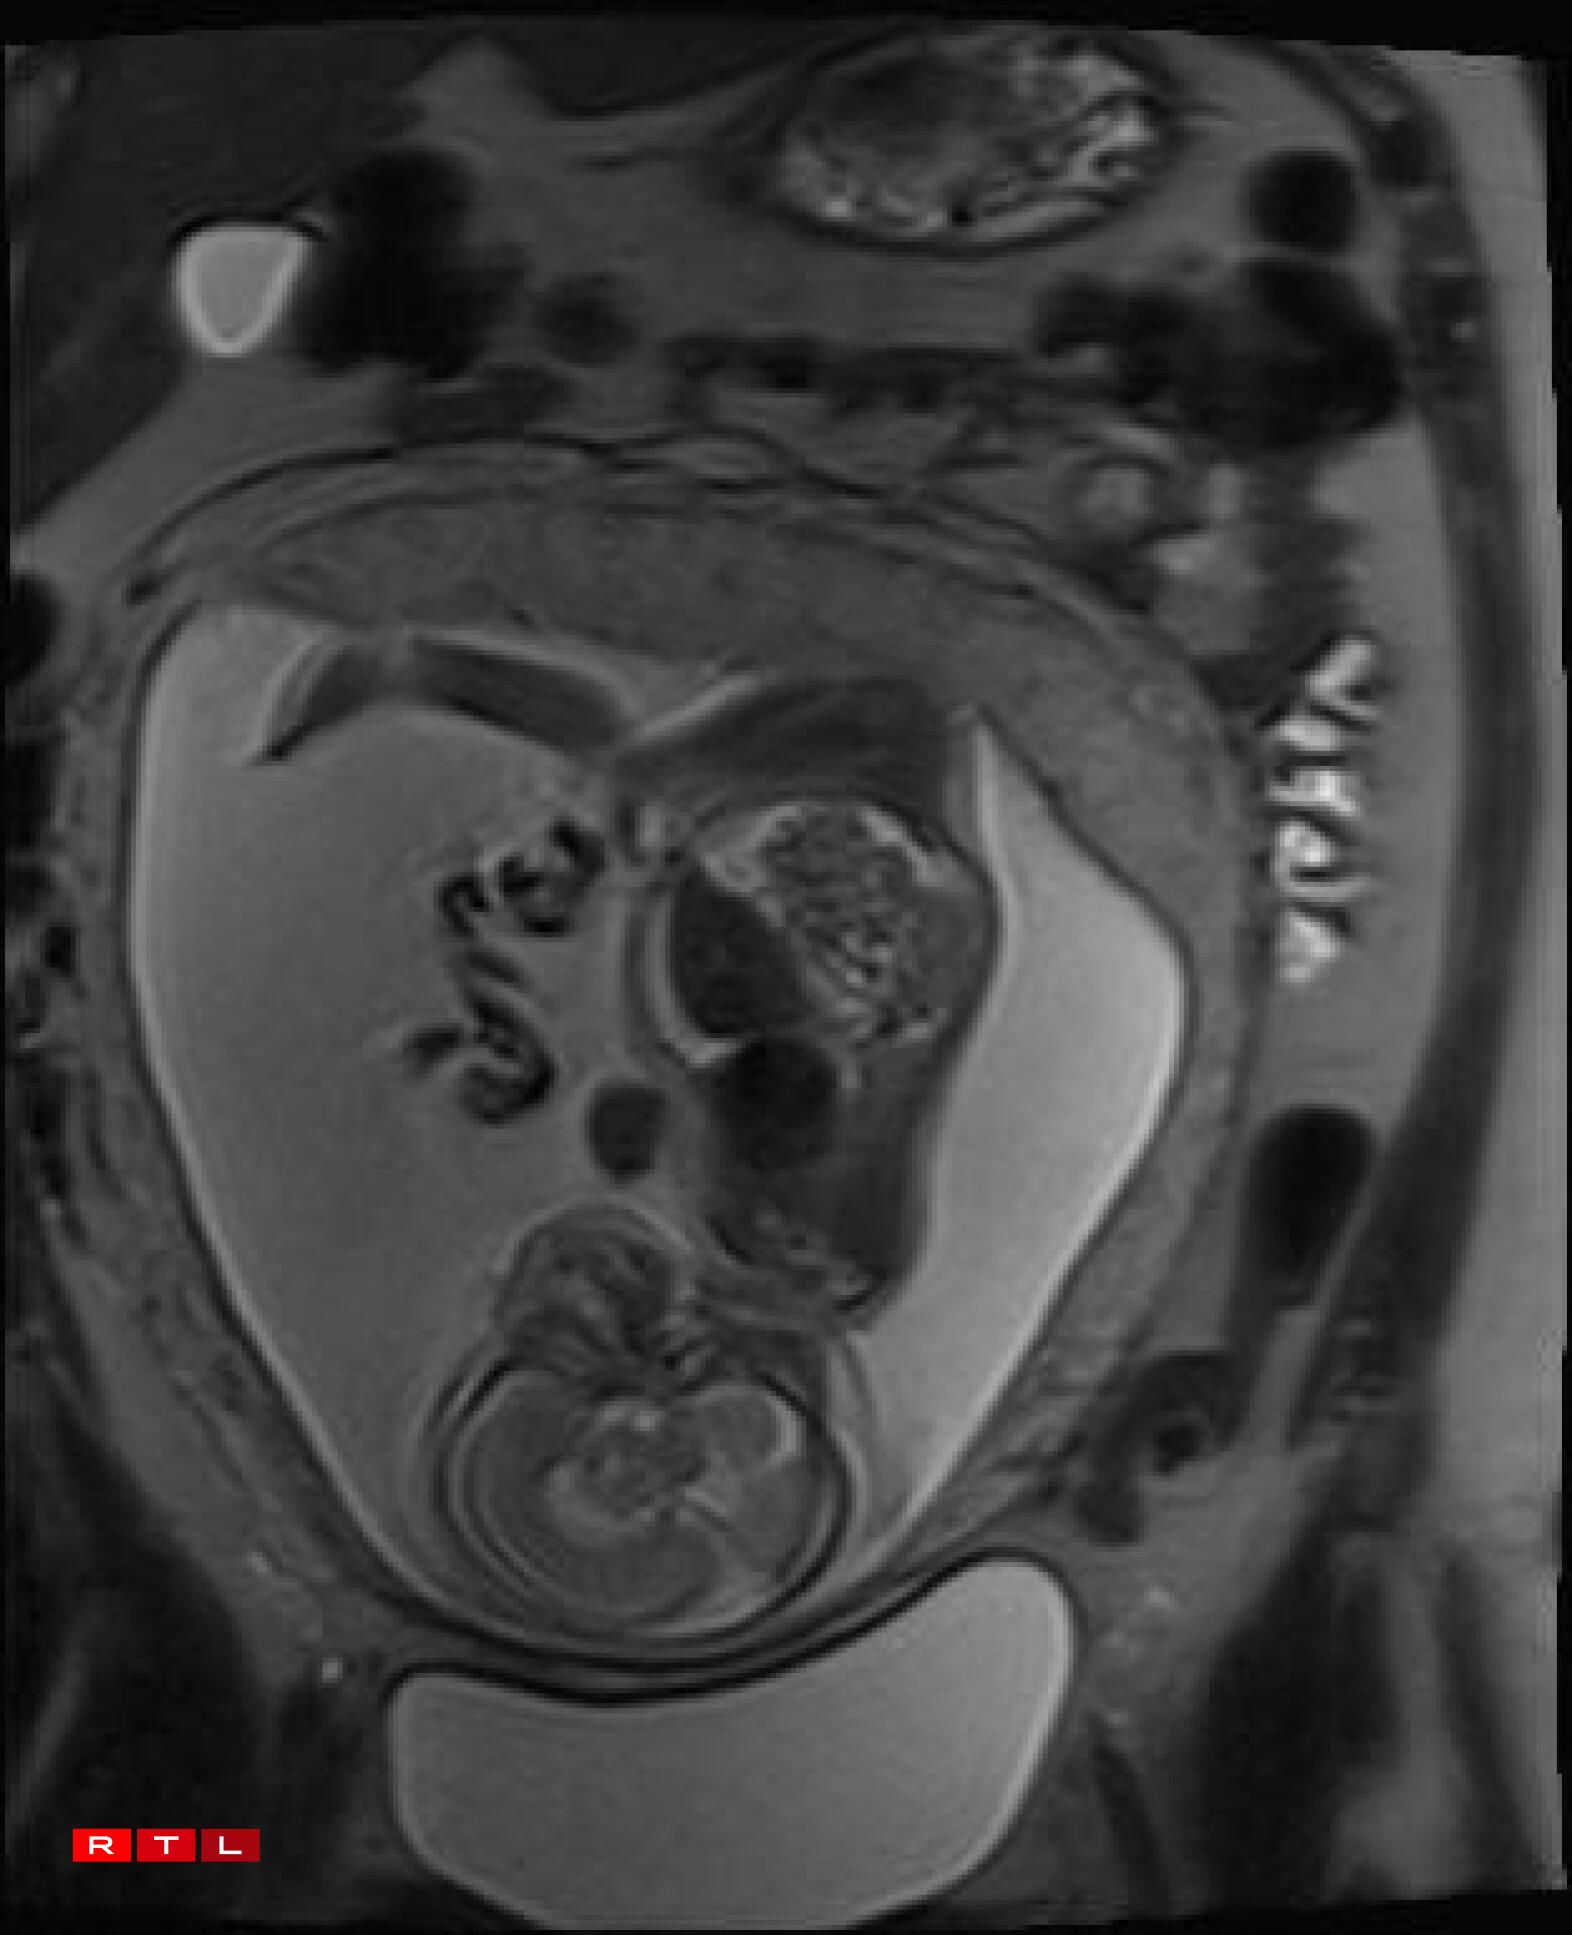

Lis was therefore referred to the Centre Hospitalier de Luxembourg (CHL), where further examinations led to a diagnosis. Noa was found to have a congenital pulmonary airway malformation (CPAM). Doctors explained that a large mass of cysts had formed in his chest, compressing his heart and disrupting his circulation. This, in turn, caused the fluid retention observed during the initial scan.

In Noa’s case, the CPAM was caused by a malformed aorta: a blood vessel had branched toward the lungs and was feeding the cysts. The condition is known as a sequestration. Professor Kohl proposed the following intervention:

“He would go through my abdomen with two small incisions to reach the amniotic sac, then pass through Noa’s chest to the heart, where he would cauterise the blood vessel that was feeding the cysts using a small electric current. From there, we could hope that the cysts would shrink and the lung could begin to develop”.